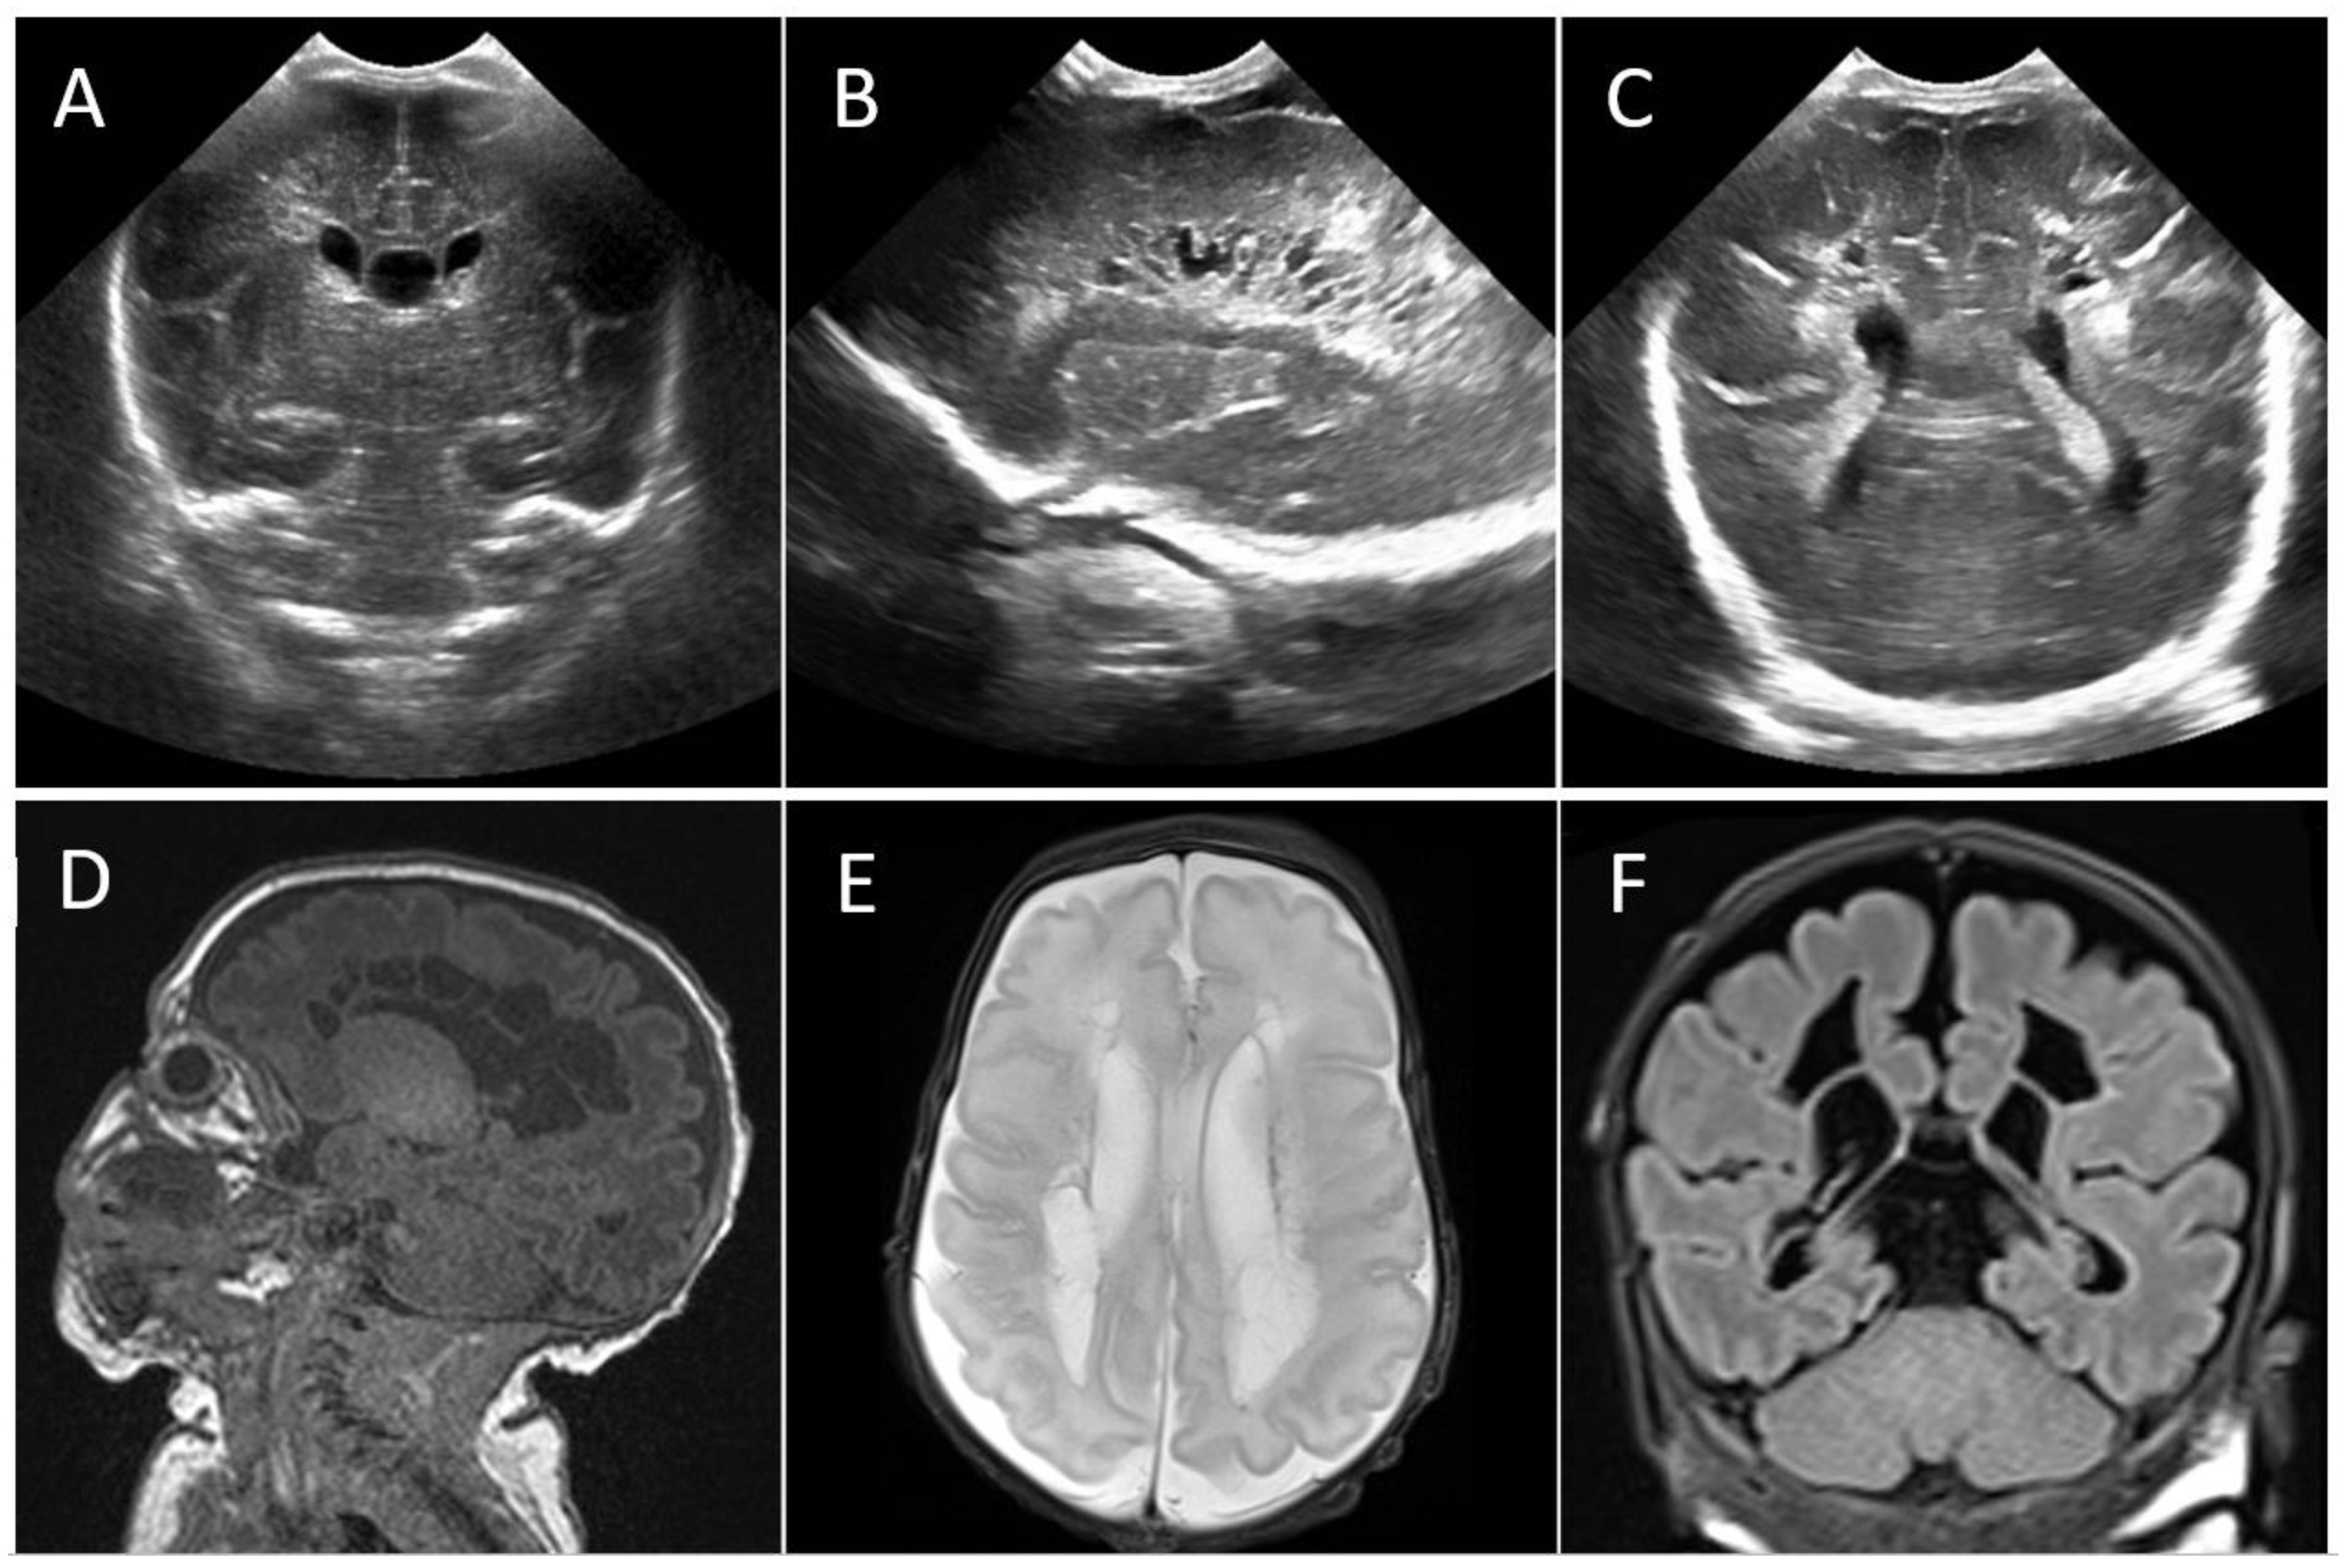

4.3.1. Case 1

4.3.2. Case 2